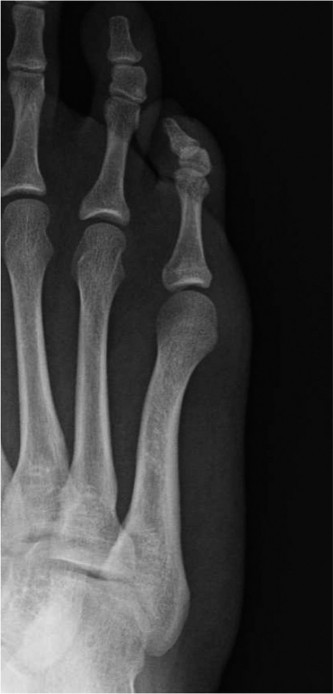

Question 29

Which of the following best describes a Jones fracture? tarsometatarsal joint. the fourth–fifth intermetatarsal articulation. fourth–fifth intermetatarsal articulation. fifth intermetatarsal articulation.

Explanation:

Fracture at the metaphyseal–diaphyseal junction of the fifth metatarsal at the level of the fourth–fifth intermetatarsal articulation. Fractures of the base of the fifth metatarsal are common. They are classified into zones according to location: Zone 1 – Proximal metaphyseal fracture of the fifth metatarsal at the level of the tarsometatarsal joint Zone 2 – Fracture at the metaphyseal–diaphyseal junction of the fifth metatarsal at the level of the fourth–fifth intermetatarsal articulation Zone 3 – Fracture at the proximal diaphysis of the fifth metatarsal distal to the level of the fourth–fifth intermetatarsal articulation The zone 2 injury is also known as a Jones fracture, after Sir Robert Jones. 216